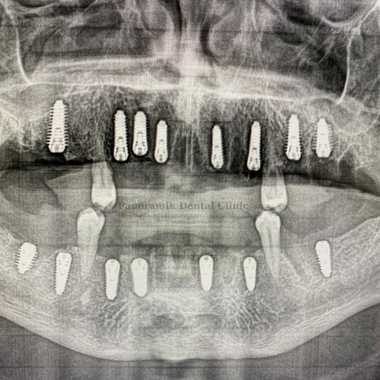

All on Eight Implants Technique

What Is All on 8 Implantation? How Is It Used?

All on 8 implants technique are used when a person is missing teeth. After implantation, a temporary denture is placed if necessary. The gums heal in about a week, and it takes three to six months of time for the bone to fully heal.

- The All on 8 implant technique allows you to place teeth on both jaws (28 teeth).